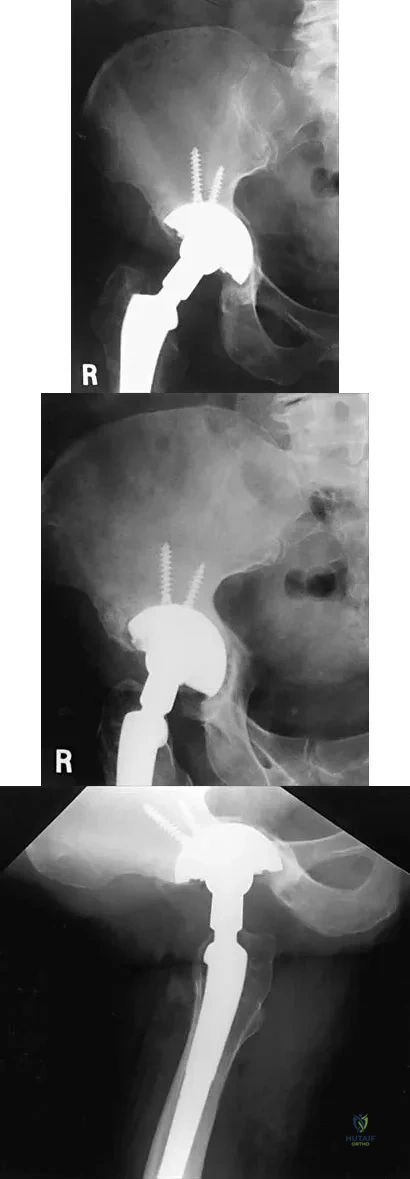

Figures 61a and 61b show the CT and MRI scans of a 40-year-old man who has hip pain. He undergoes total hip arthroplasty and curettage and cementation of the lesion as shown in Figure 61c. Histopathologic photomicrographs of the curettage specimen are shown in Figures 61d and 61e. What is the best course of treatment?

Explanation